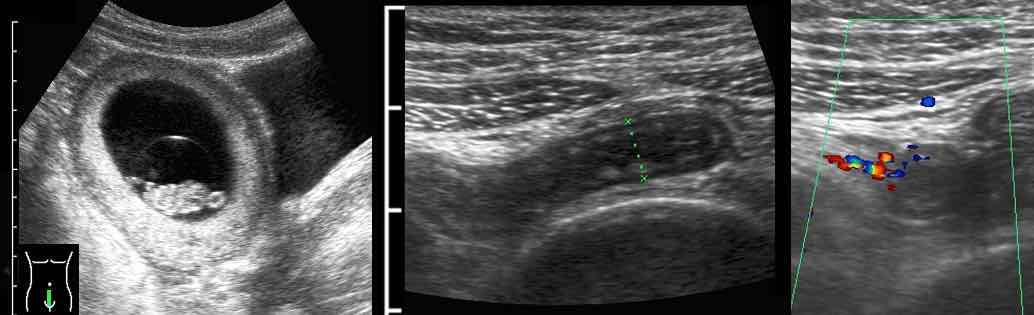

Ở người phụ nữ mang thai 11 tuần này, siêu âm xác nhận thai trong tử cung còn nguyên vẹn đồng thời phát hiện viêm ruột thừa cấp.

Lưu ý sự khác biệt về thang đo cm.

Phẫu thuật nội soi cắt bỏ ruột thừa viêm đã được thực hiện thành công.

Ở người phụ nữ mang thai và béo phì này, một ruột thừa có thể đang viêm (mũi tên kèm dấu hỏi) được quan sát thấy khi ấn mạnh sâu xuống vùng tiểu khung.

Siêu âm qua đường âm đạo tiếp theo cho thấy một ruột thừa đang viêm chứa đầy mủ, nằm trong vòng 1 cm so với đầu dò âm đạo.